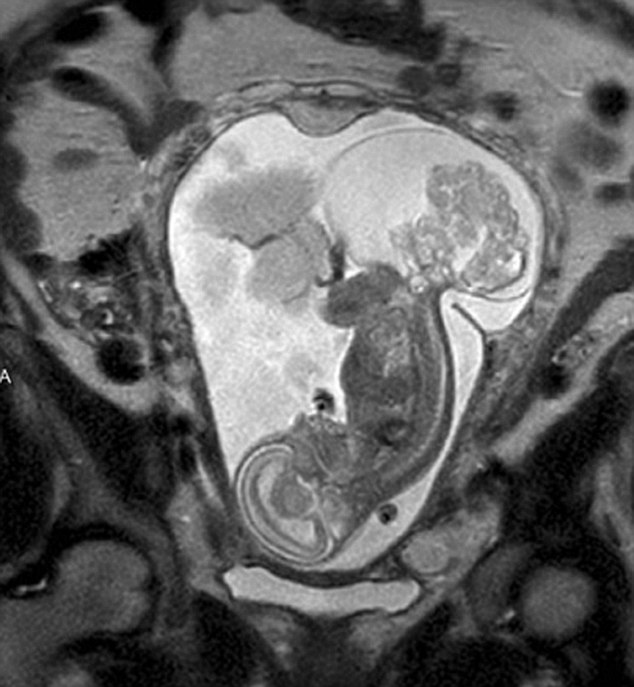

【環(huán)球網(wǎng)綜合報道】據(jù)英國《每日郵報》10月23日報道,美國得克薩斯州布蘭諾市的女子瑪格麗特·伯默(Margaret Boemer)懷孕16周時去做產(chǎn)檢,不幸被告知胎兒尾骨上長有腫瘤,她與醫(yī)生商量后決定先將胎兒取出進行腫瘤切除手術(shù),再將其送回子宮繼續(xù)孕育。最終手術(shù)圓滿成功,12周后胎兒足月出生。

瑪格麗特稱自己當(dāng)時聽到產(chǎn)檢結(jié)果時十分害怕。“醫(yī)生說寶寶長了骶尾部畸胎瘤。我們很震驚,很害怕,因為我們根本不知道這個什么瘤到底意味著什么。”隨著時間流逝,腫瘤越來越大,胎兒滿23周時腫瘤已危及其性命。醫(yī)生告訴瑪格麗特,若想胎兒存活,只能將胎兒取出進行手術(shù),然后再放回子宮,否則只能立即終止孕期。“這很容易做決定:讓腫瘤奪去孩子性命,或是給孩子存活的機會。我們當(dāng)然選擇后者。”瑪格麗特說。

醫(yī)生將胎兒取出20分鐘后,便放回母體子宮。12周后,寶寶足月出生。瑪格麗特稱:“這可以說是她的第二次出生了。只要她有機會活下來,我愿意承受所有風(fēng)險。”(實習(xí)編譯:高睿 審稿:朱盈庫)